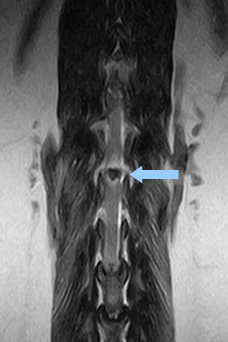

![]() 胸腰部MRI検査 矢印が飛び出した椎間板 下から上の脊髄神経を圧迫している |